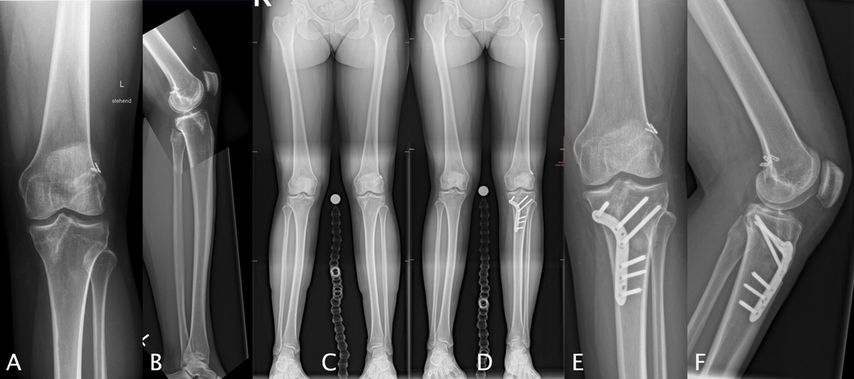

Knöcherne Achsfehlstellungen der unteren Extremität beeinflussen die Biomechanik des Kniegelenks maßgeblich und stellen relevante Risikofaktoren für Rupturen des vorderen Kreuzbandes (VKB) sowie für das Versagen von VKB-Rekonstruktionen dar. Insbesondere im Revisionssetting rücken sagittale und koronare Fehlstellungen zunehmend in den Fokus der differenzierten Therapieplanung.